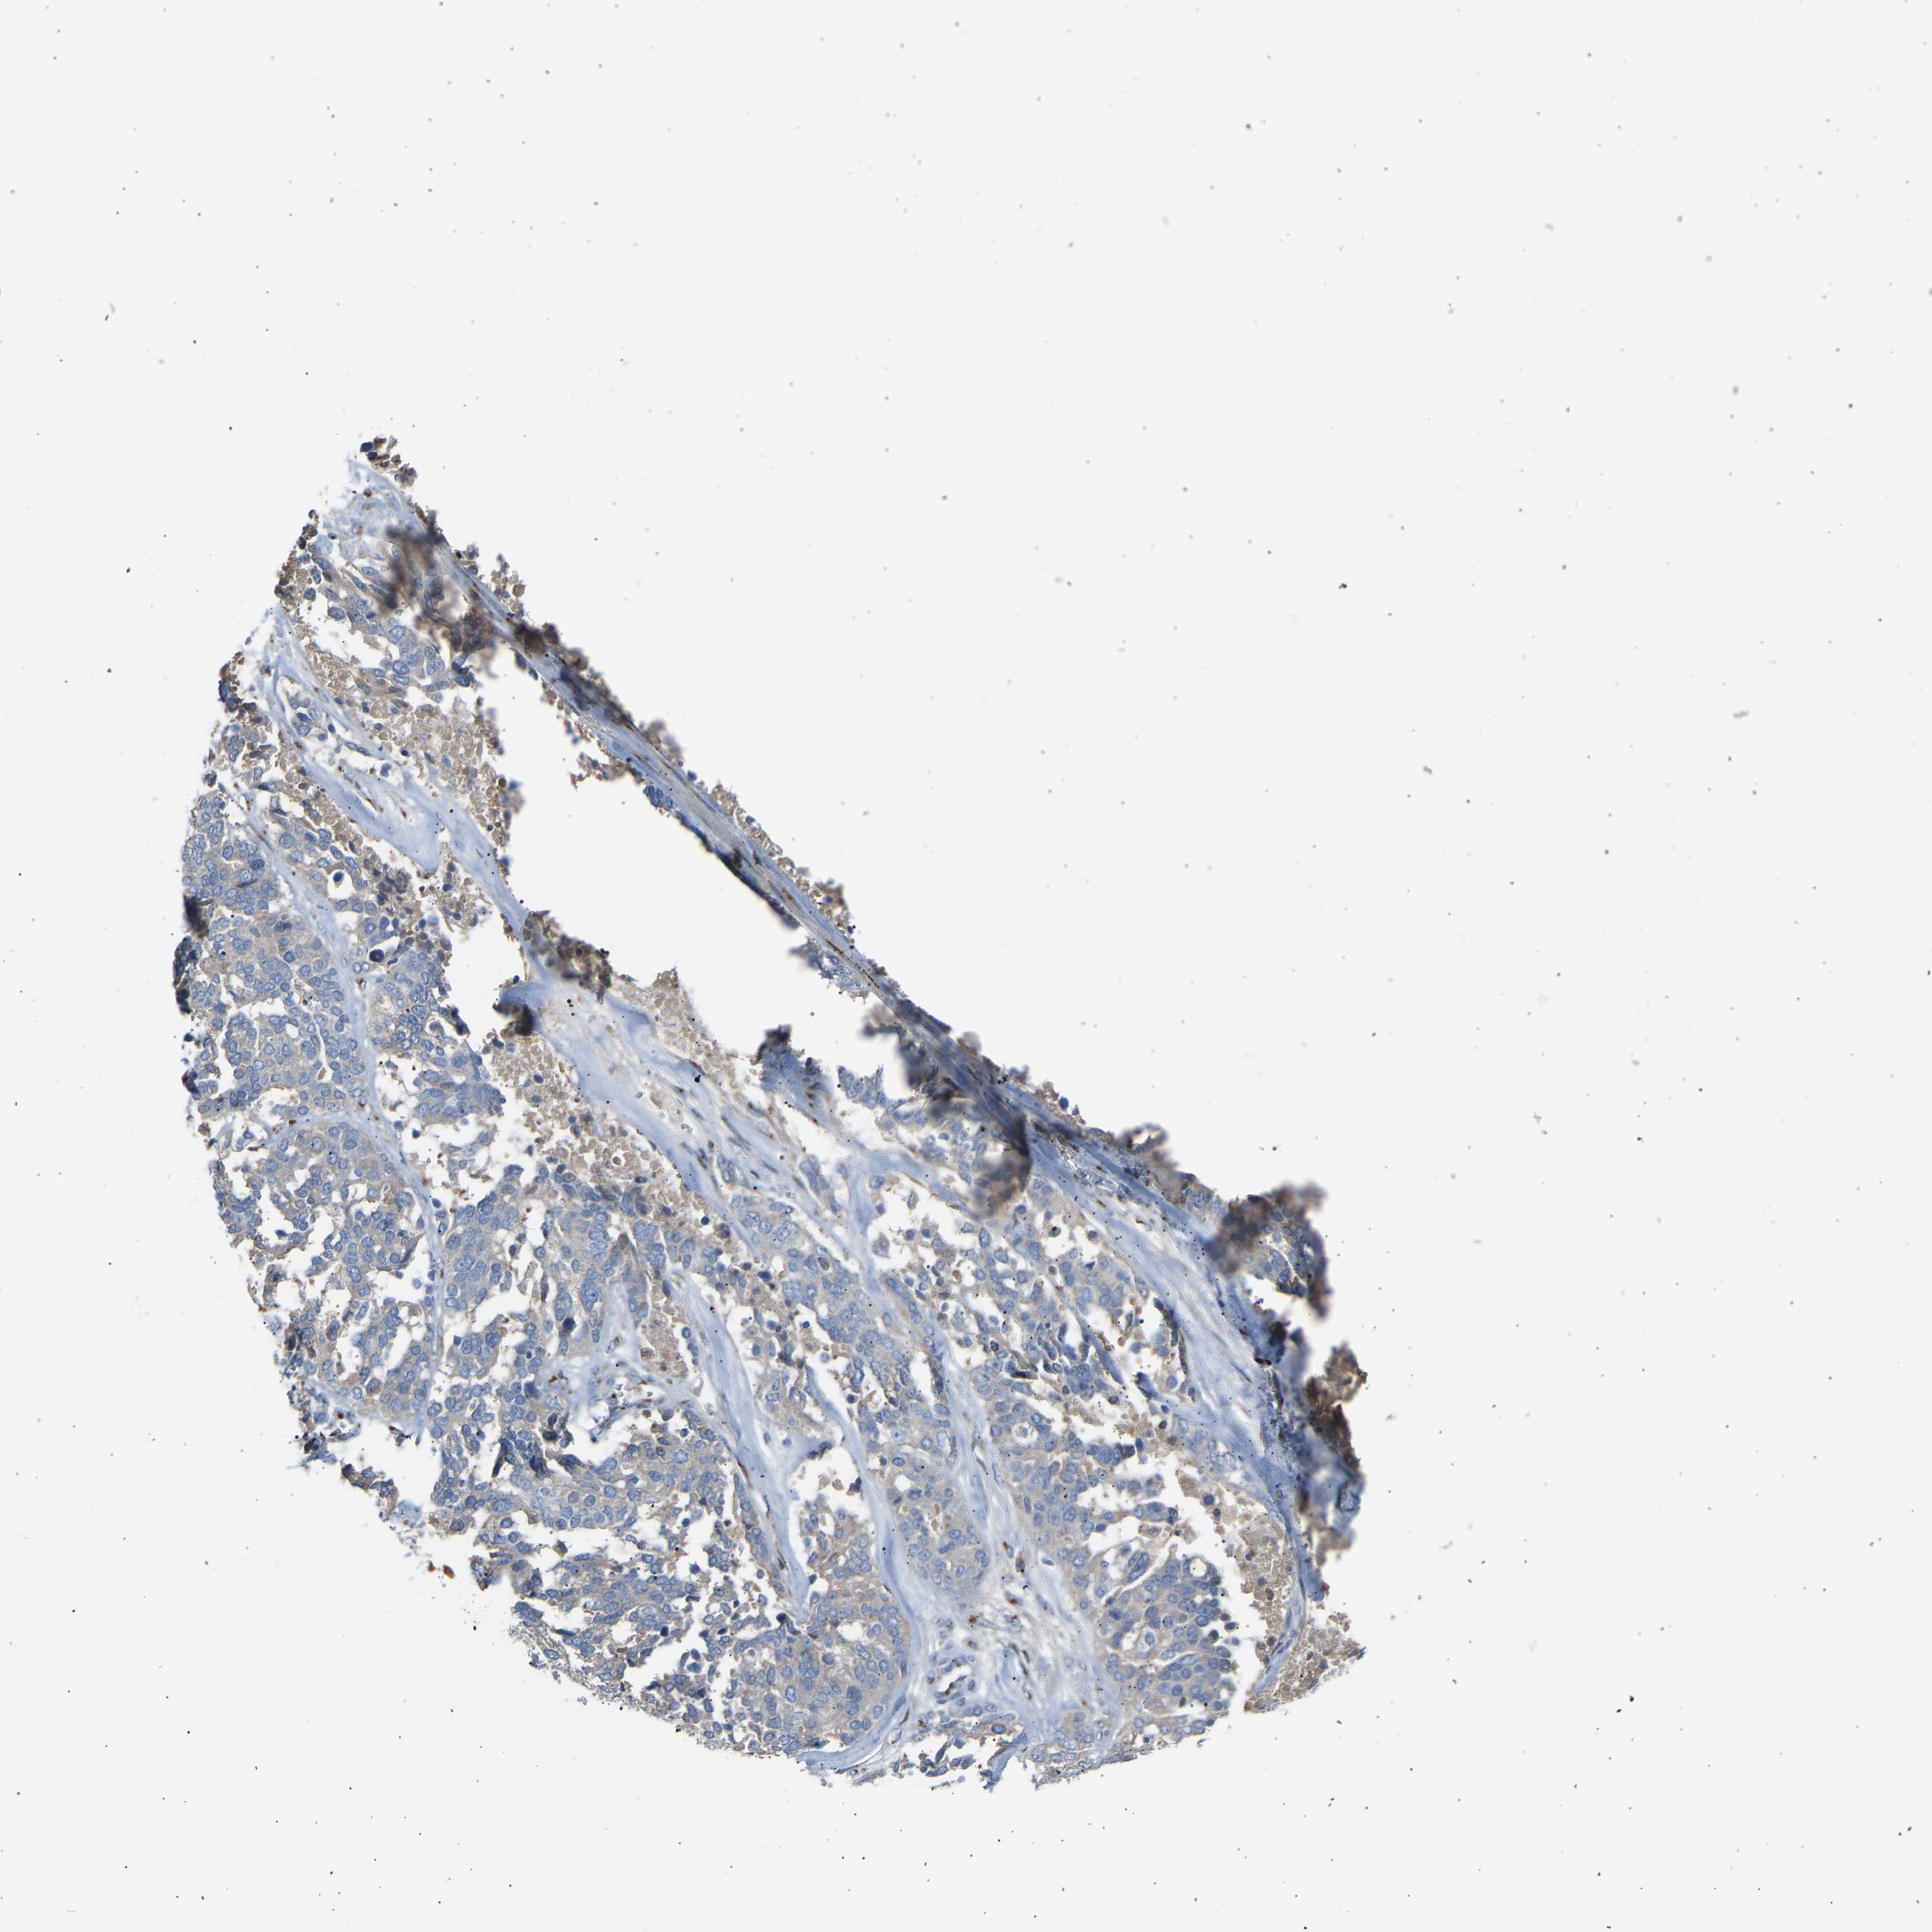

OVARIAN CANCER - Protein expressioni

A mouse-over function shows sample information and annotation data. Click on an image to view it in a full screen mode. Samples can be filtered based on level of antibody staining by selecting one or several of the following categories: high, medium, low and not detected. The assay and annotation is described here.

Note that samples used for immunohistochemistry by the Human Protein Atlas do not correspond to samples in the TCGA dataset.

Antibody stainingi

Antibody staining in the annotated cell types in the current human tissue is reported as not detected, low, medium, or high, based on conventional immunohistochemistry profiling in selected tissues. This score is based on the combination of the staining intensity and fraction of stained cells.

Each image is clickable and will lead to virtual microscopy that enables deeper exploration of all samples and also displays staining intensity scores, fraction scores and subcellular localization as well as patient and tissue information for each sample.

Antibody HPA020060

Staining

High

Medium

Low

Not detected

Intensity

Strong

Moderate

Weak

Negative

Quantity

>75%

75%-25%

<25%

None

Location

Nuclear

Cytoplasmic/membranous

Cytoplasmic/membranous,nuclear

Cystadenocarcinoma, serous, NOS

Carcinoma, endometroid

Cystadenocarcinoma, mucinous, NOS

Carcinoma, NOS